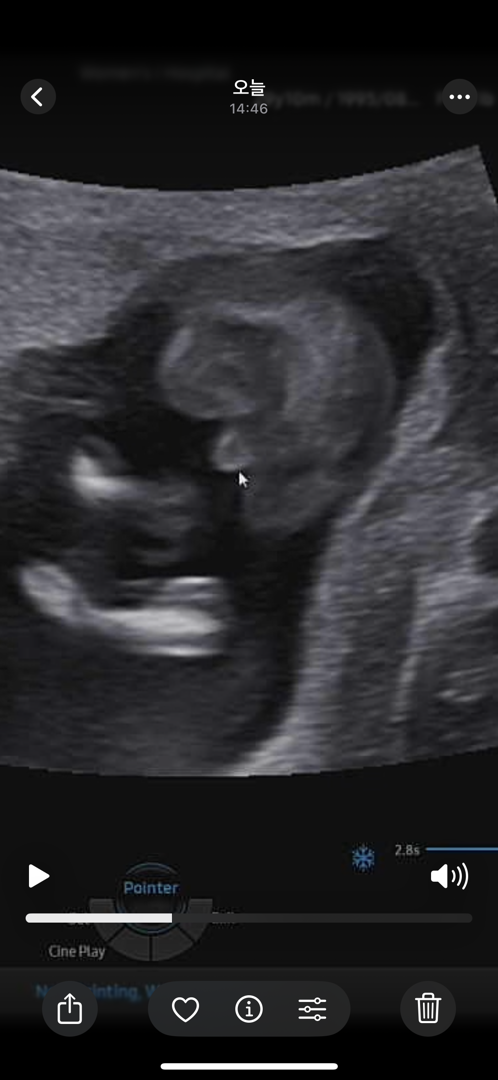

다리사이에 뭐가 있죠? 하시면서 가리키셨는데.. 15주 3일차인데 ㅠㅠ 큰 이변은 없겠죠..?🥲